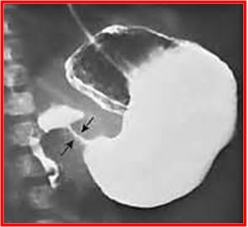

诊 断

◇临床表现:典型的呕吐,右上腹扪及肿块即可确诊

◇如未扪及肿块,B超指数不肯定,可行GI检查:

胃扩张

胃蠕动增强

幽门管细长线状

排空延迟